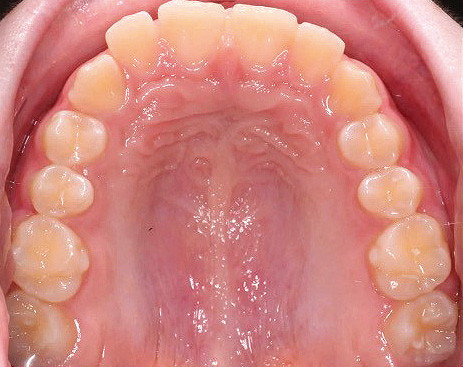

Klinisches Fallbeispiel 2 (Abb. 2a–y)

Distalbiss und tiefer Biss bei einem zwölfjährigen Mädchen. Die Behandlung erfolgte mit Invisalign und Precision Wings. Insgesamt waren zwei Schienensätze notwendig. Die Gesamtbehandlung dauerte 18 Monate.Bei der Planung des ClinCheck wurde der tiefe Biss vorwiegend über eine Intrusion der Unterkieferfront behoben, um die Lachlinie der Patientin nicht negativ zu beeinflussen. Die Oberkieferfront wurde nur retrudiert, jedoch vertikal nicht intrudiert. Während der Phase des Mandibular Advancement wurde die Wirkung der Precision Wings durch den Einsatz von Klasse II-Gummizügen unterstützt. Schlussendlich wurde auch der hängenden Okklusionsebene durch eine einseitige Intrusion der Molaren im ersten Quadranten Rechnung getragen.